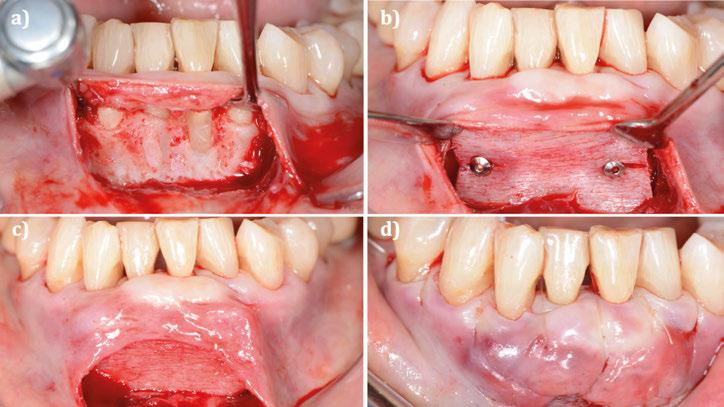

Figura 3. Intervención quirúrgica del caso clínico 1. a) situación clínica basal; b) colgajo de acceso apical vestibular y medición del defecto; c) posicionamiento ideal del injerto de tejido conectivo autólogo; d) sutura del injerto de tejido conectivo autólogo al colgajo a través del acceso apical vestibular.

Figura 4. Intervención quirúrgica del caso clínico 1. a) posición del injerto suturado a través del colgajo de acceso apical vestibular; b) utilización de aloinjerto particulado (OraGRAFT® Aloinjerto Cortical Particulado MIX 70% Mineralizado / 30% Desmineralizado) para rellenar el interior del defecto y cubrir la dehiscencia ósea; c) cobertura de la dehiscencia ósea con el aloinjerto particulado; d) customización de la lámina de cortical acorde a las características del defecto (Lámina de cortical desmineralizada Cortiflex® Salugraft Dental).

Se realiza una incisión biselada hacia coronal a espesor total en forma de parábola cóncava a apical en la mucosa labial con una hoja de bisturí no 10 alejada del fondo de vestíbulo actual. Es necesario destacar que la línea de incisión que estamos realizando se convertirá en el nuevo fondo de vestíbulo al final del procedimiento. El bisturí debe estar orientado a 45o al eje apico-coronal de los dientes. Además, la extensión mesio-distal de la incisión será acorde al número de recesiones adyacentes a tratar, debiendo extendernos idealmente un diente más a cada lado.

Una vez preparado el lecho receptor, dada la existencia de una situación combinada de recesión gingival y una dehiscencia ósea vestibular con pérdida de inserción interproximal, se opta por la utilización combinada de un injerto de tejido conectivo autólogo tuberositario, un sustituto de origen alogénico (Lámina de cortical desmineralizada Cortiflex® Salugraft Dental) que se fija mediante dos chinchetas a ambos lados, cubriendo un injerto óseo de origen alogénico particulado (OraGRAFT® Aloinjerto Cortical Particulado MIX 70% Mineralizado / 30% Desmineralizado). Primero se suturó el injerto de tejido conectivo autólogo al colgajo, después se colocaron las partículas

de injerto óseo y, posteriormente, se fijó la lámina cortical.

Por último, se sutura la línea de incisión a fondo de vestíbulo dando puntos anclados al periostio, permitiendo, con escasos puntos de sutura, cerrar el acceso realizado y dejando la mucosa labial cicatrizando por segunda intención.

Estos puntos se dan atravesando con la sutura el colgajo en dirección corono-apical y, posteriormente, atravesando el periostio en perpendicular en dirección mesio-distal.